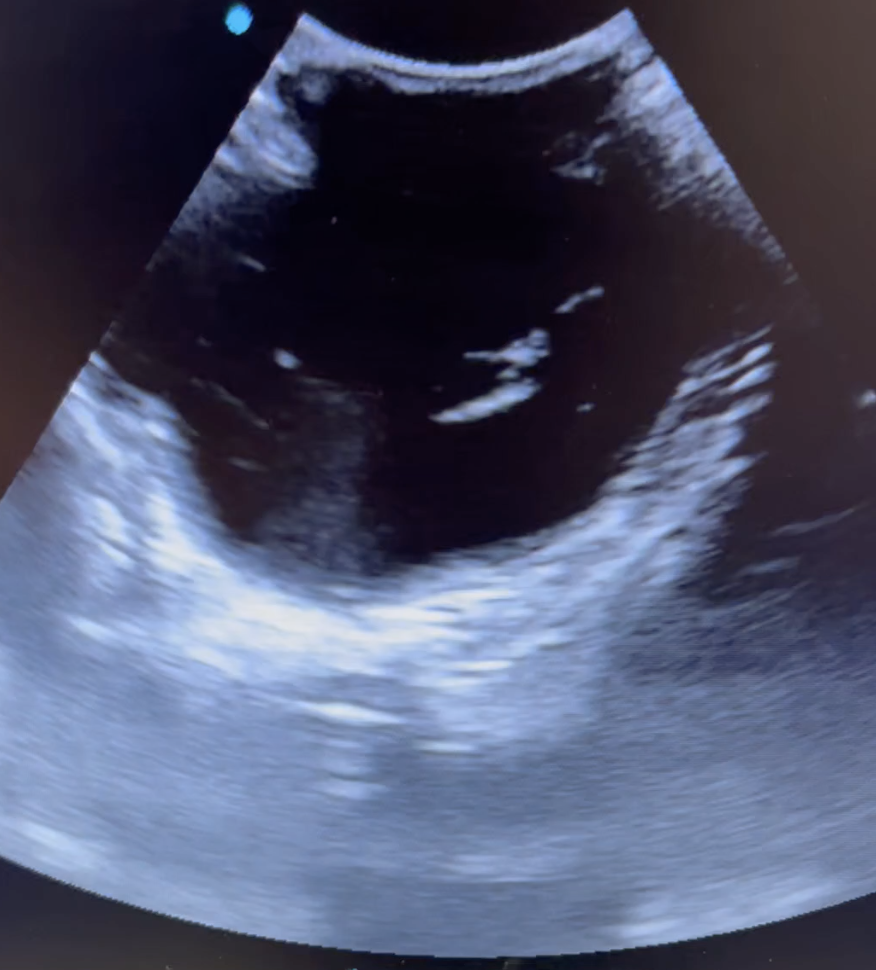

This feline scan was performed at 52 days following a 30 day scan suggesting a singleton kitten. The linear probe was used. The mother delivered the kitten without issue.